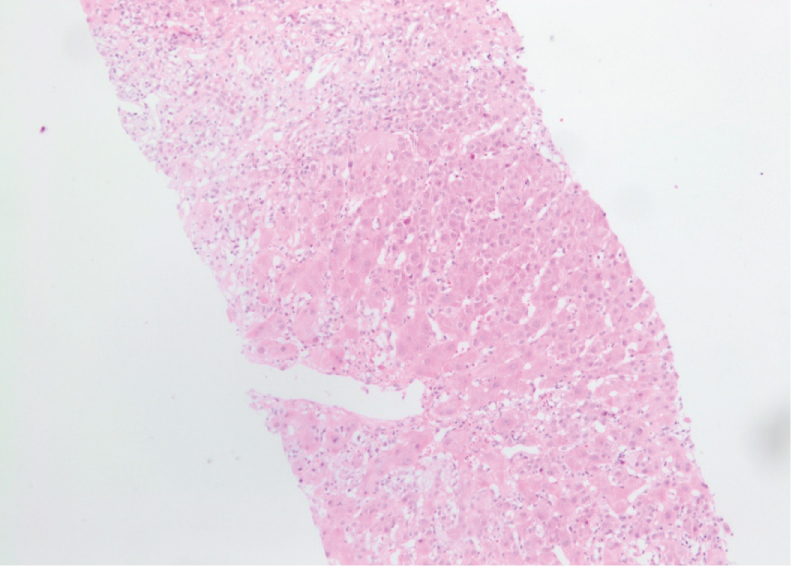

Liver biopsy showed acute hepatitis with severe inflammatory activity. The hepatic architecture is very reworked with 12 enlarged fibroadenomatous portal spaces, seat of fibrosis more or less important with a tendency to confluence (bridging) inter-portal. The lobules are dissociated by a polymorphic inflammatory infiltrate with extensive hepatocyte necrosis (< 50% of the portal circumference) and Councilman body formation. The remaining hepatocytes are surrounded by edematous fibrosis (Figure 1).

Figure 1: Beginning of cirrhotic lobulations related to a very active hepatitis, compatible with an autoimmune origin. Salem Ch, Makhoul E, Murr T, et al. View Figure 1

Fortunately, several histological and clinical features can differentiate AIH from SLE. The presence of cirrhosis or periportal (interface) hepatitis, periportal piecemeal necrosis associated variably with lobular activity, and rosette formation of liver cells support the diagnosis of AIH, but do not exclude SLE. The presence of only lobular hepatitis is more compatible with SLE. In both "lupus hepatitis" (or "SLE hepatitis") and treated AIH, the inflammatory infiltrate consists mainly of lymphocytes, whereas in untreated AIH, these cells are mixed with plasma cells [5]. Our patient had acute hepatitis with severe inflammatory activity characterized a hepatic architecture with 12 enlarged fibroadenomatous portal spaces, seat of fibrosis more or less important with a tendency to confluence (bridging) inter-portal. The lobules are dissociated by a polymorphic inflammatory infiltrate with extensive hepatocyte necrosis (< 50% of the portal circumference) and Councilman body formation.

While these markers may help to segregate AIH coincident with SLE serologically, liver histopathology represents the key feature that distinguishes AIH in SLE from nonspecific hepatic involvement in SLE. In patients with AIH liver histopathology shows characteristic lesions, such as interface hepatitis, rosetting of hepatocytes, emperipolesis and -consecutive to inflammation-fibrosis (Figure 2).

Figure 2: Typical histopathology of a patient with autoimmune hepatitis. Cirrhotic changes of the liver parenchyma with interface hepatitis. The portal and periportal inflammatory infiltrate are composed of lymphocytes, monocytes/macrophages and plasma cells (haematoxylin and eosin staining × 200) [4]. View Figure 2